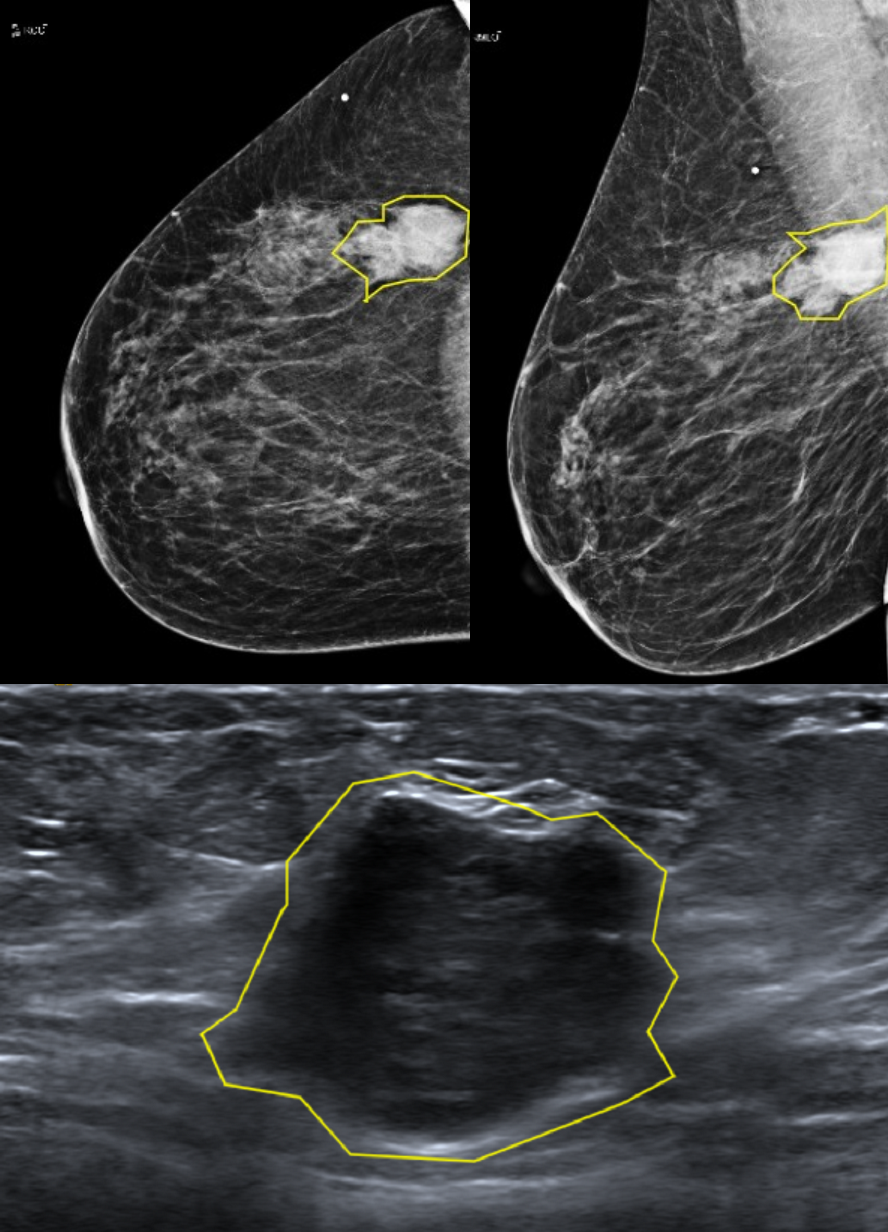

Although combining mammography and ultrasound imaging for breast cancer screenings is a common practice, to the best of our knowledge there are no public datasets containing corresponding lesions from both modalities. Therefore, we created our own retrospective dataset of 153 biopsy-proven lesions, consisting of 73 malignant and 80 benign cases. For each lesion, corresponding mammography and ultrasound images were contoured by an expert breast radiologist, with a biopsy proven labelling. Figure 2 demonstrates a sample from the dataset.

Refer to caption

Figure 2: Matched malignant lesion contouring in both modalities.